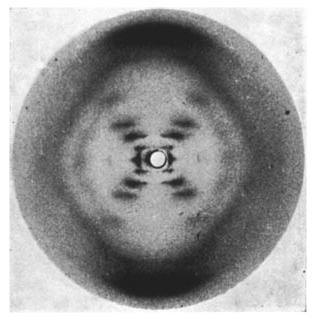

• Invención de los Rayos X

Invención de los Rayos X

Descubrimiento de los rayos X en 1895. A finales del siglo XIX, en 1895, Wilhelm Conrad Röntgen (1845-1923), científico alemán de la Universidad de Würzburg, descubrió una radiación (de origen desconocido en aquel momento, y de ahí su nombre de rayos X) que tenía la propiedad de penetrar los cuerpos opacos.